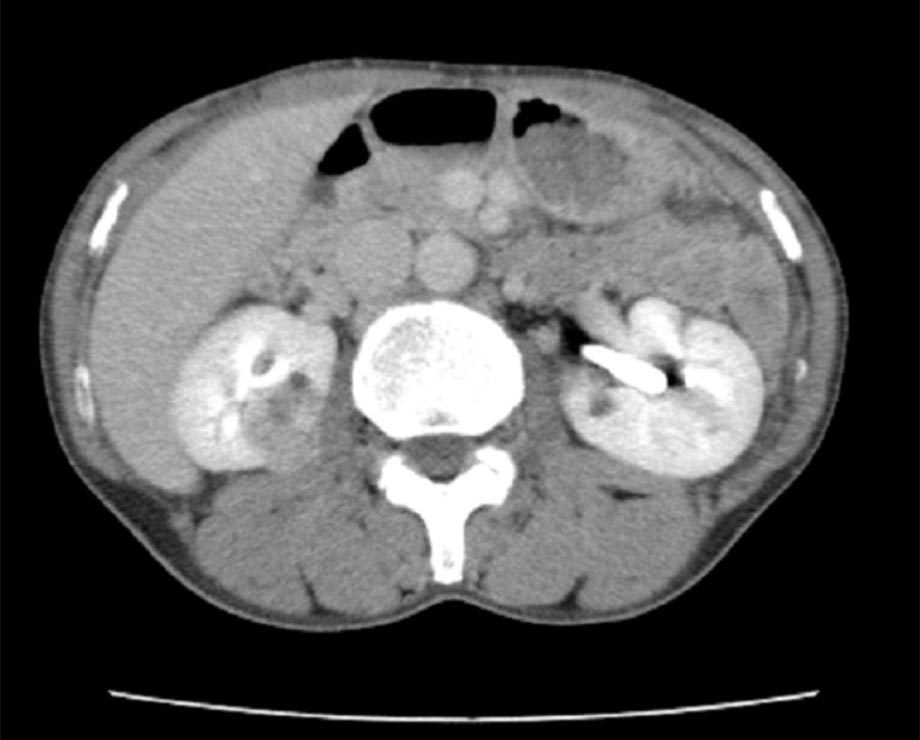

- 腎がん